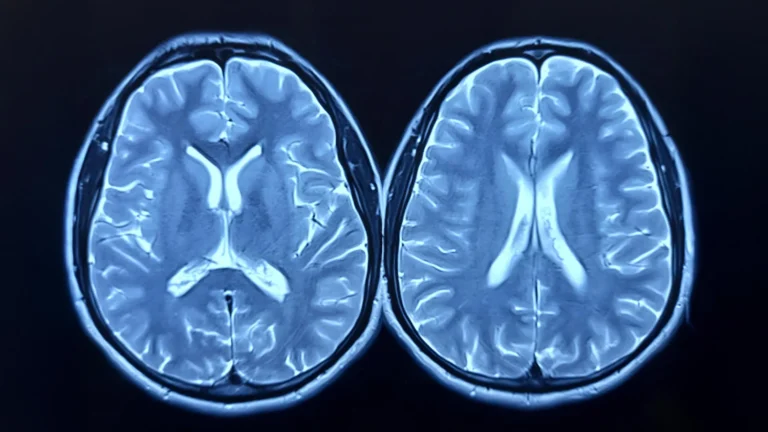

A year of consistent, moderate-to-vigorous aerobic exercise can contribute to a brain appearing biologically younger, according to...